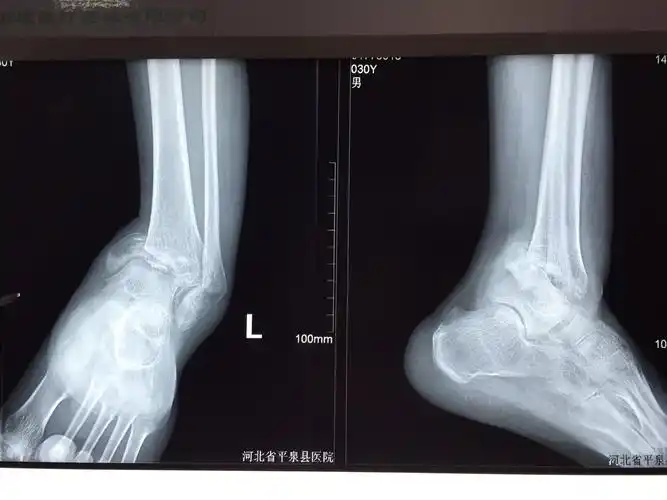

复位前正侧位x光片